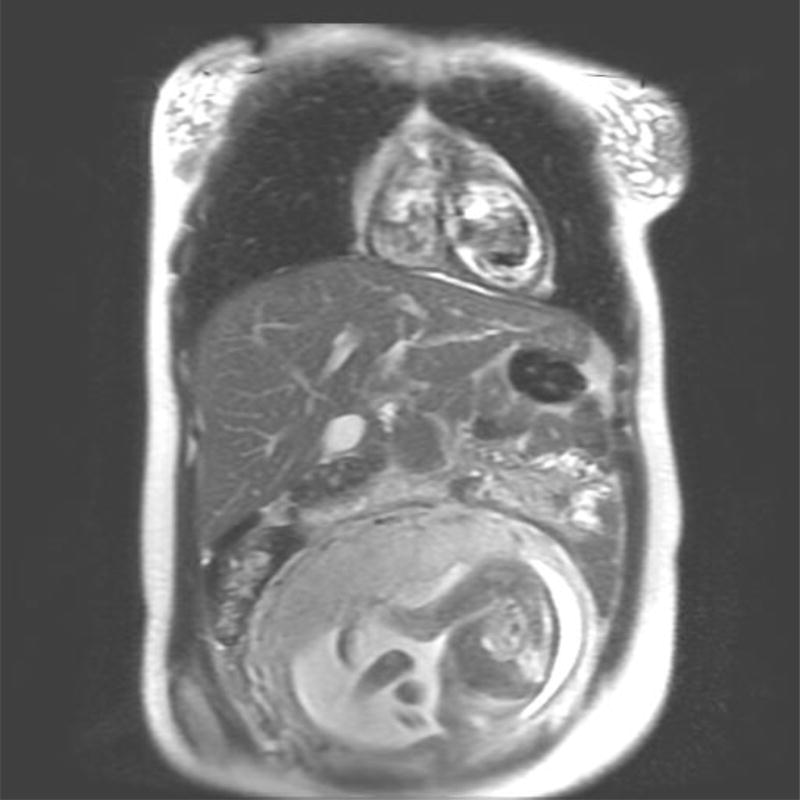

Imaging of the pregnant patient for diagnosis and response assessment poses a challenge to the multi-disciplinary team. Magnetic resonance imaging (MRI) is regarded as the modality of choice for acquisition of cross sectional imaging, as no studies to date have demonstrated adverse effects on the fetus from MRI (Figure 1) [5]. Gadolinium, which has been shown to have teratogenic effects in animal models, is not recommended for use during pregnancy [6]. Iodine based contrast should also be avoided during pregnancy. Computed tomography (CT), which employs ionizing radiation is discouraged, although it is possible to reduce abdominopelvic dose with various techniques including abdominal shielding and lower dose protocols for image acquisition [7].

Figure 1.

Non-contrasted MRI performed for disease staging in a 28 year old patient diagnosed with cHL.

A. Axial T1 Non-Contrasted image of the chest

B. Coronal T2 weighted image of the chest, abdomen and pelvis